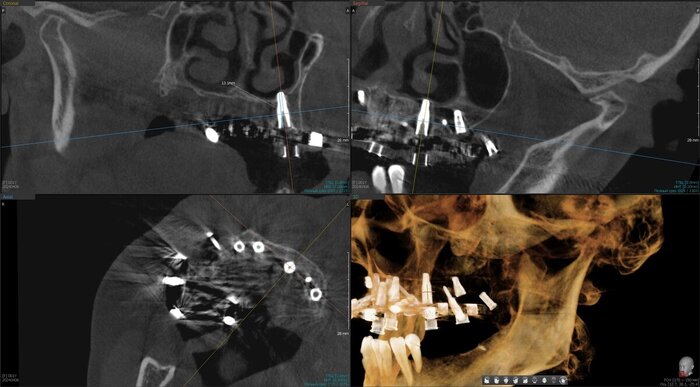

Получилось так, что сверху всего 8 зубов, по 4 с каждой стороны. Чёрная точка (которую вы точно увидите, скос эмали на зубе 1.1) - конструктивные особенности, всё это будет закрыто пломбировочным материалом. Зуб 1.1 - дополнительный имлантат, который потом планируем убрать. Он нужен лишь для усиления, ибо торк полноценный был получен только на одном из остальных 6-ти установленных.

Напоминаю - протезы временные адаптационные

Так же важный момент - верхний протез соприкасается с нижним только в точках полученного торка (их всего 2), остальное "на весу" и жевать не способно.

Рекомендации - мягкая, жидкая пища 4 месяца! Это важно.

Низ - всё ок.